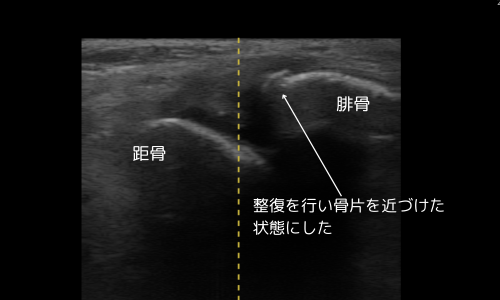

- 屈曲整復による骨片整復

- L字シーネ固定、アイシング